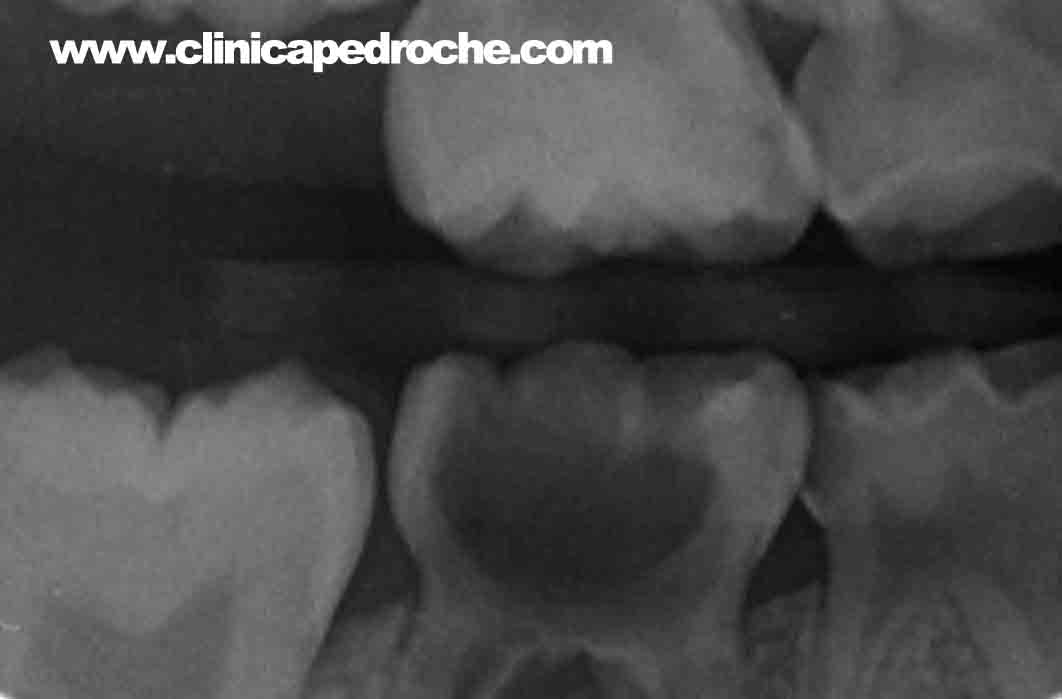

Las muelas (piezas posteriores) recién erupcionadas, sean de leche (erupcionan del año y medio a los dos años y medio) o definitivas (erupcionan a los 5-7 años), son más susceptibles a sufrir deterioro por caries. Por ello es esencial limpiar las superficies oclusales de las muelas que son las que trituran los alimentos. Posteriormente también hay que poner atención si quedan restos entre medias de las mismas para que no se hagan caries entre dos dientes que sólo se verán con radiografías en las revisiones semestrales que hará su odontopediatra o cuando el deterioro sea muy grande por lo que se romperán y los padres apreciaran a simple vista el enorme agujero.

Caries detectada con radiografía en el segundo molar temporal mandíbular por

empaquetamiento de comida entre los molares (segundo inferior por la izquierda)